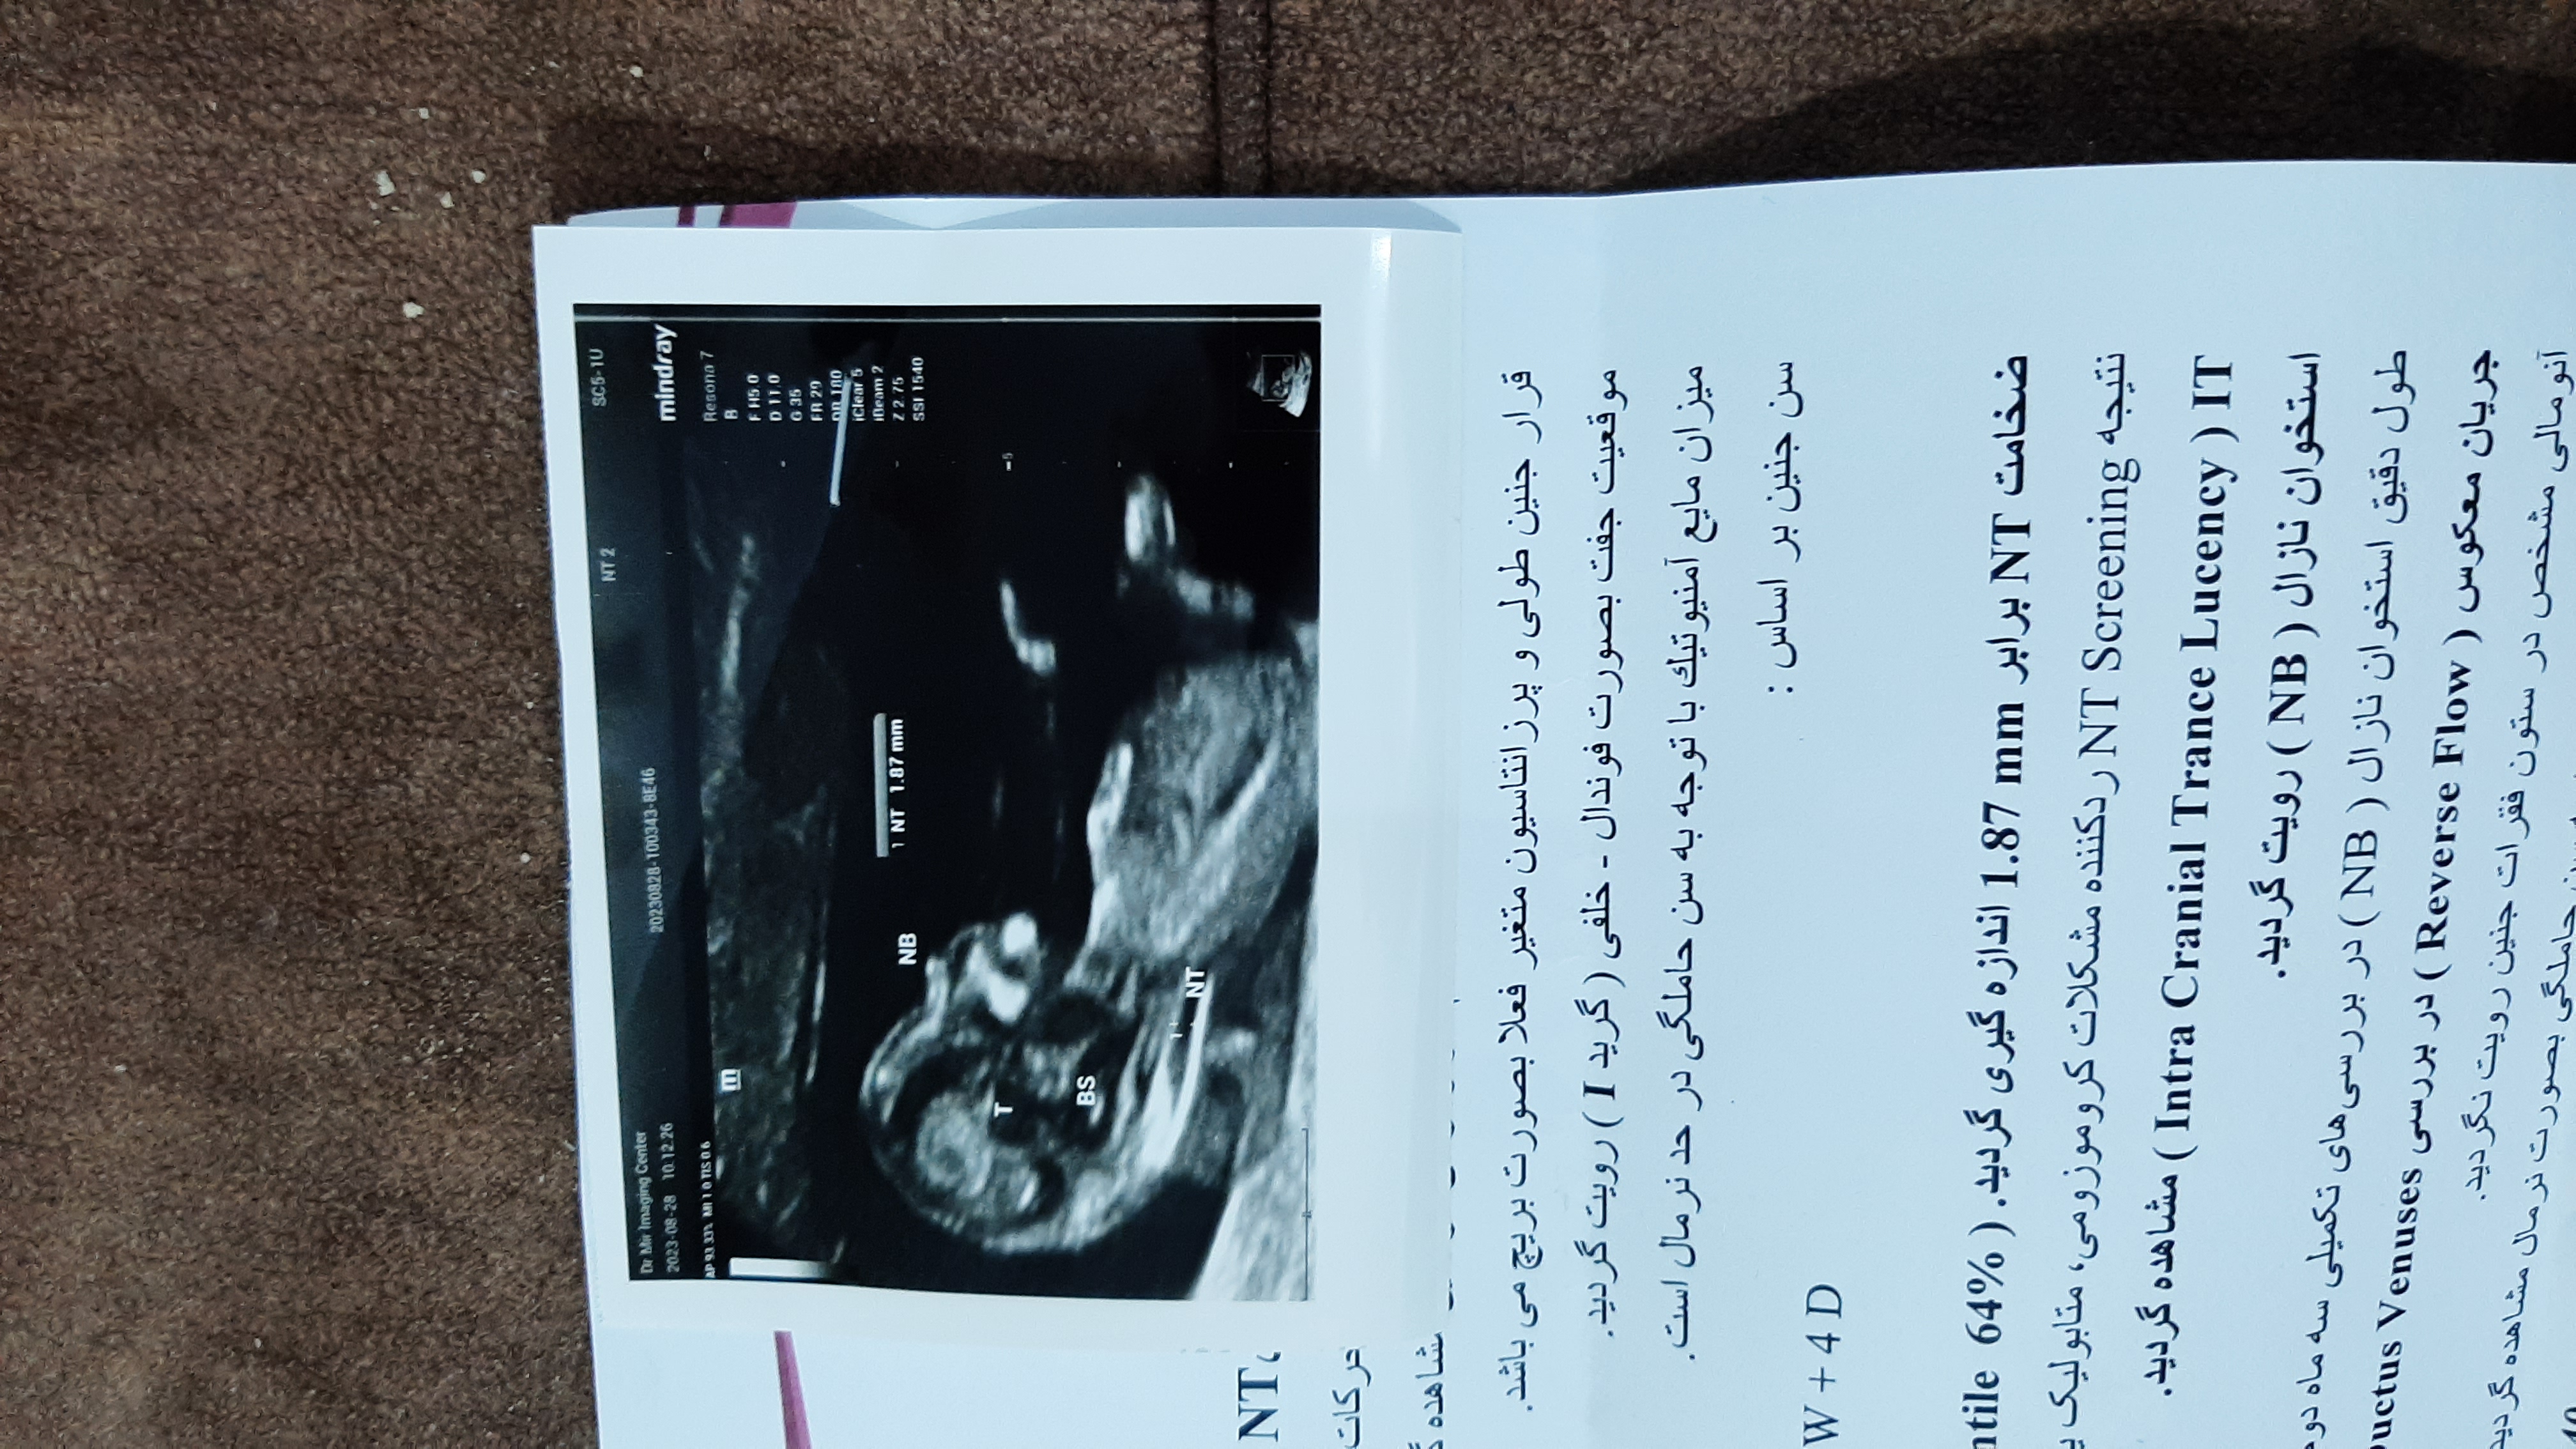

چرا توی اینستا بر اساس nubتعیین جنسیت میکنن دنبالچه بچه معلومه .ولی میری سونو چیزی توی عکس مشخص نیست .مثلا میگن زاویه 30بسازه پسر موازی باشه دختر